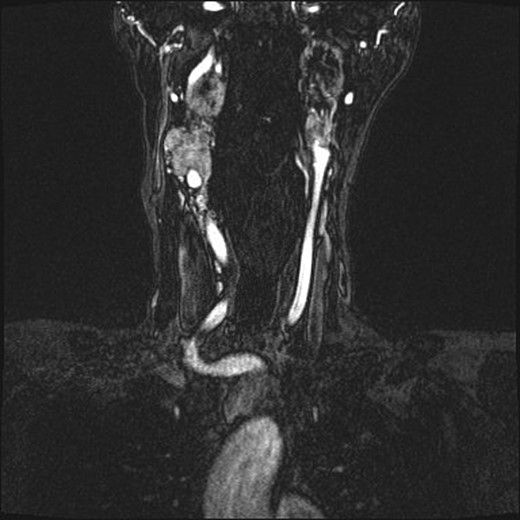

Repeat magnetic resonance imaging (Figs. 3 and 4) showed increased left-sided carotid PGL, significant extension into the jugular foramen and skull base, and associated high-grade tumor compromise of the left internal carotid artery; no radiologic evidence suggested intracranial ischemic sequelae. Computed tomographic (CT) imaging showed infiltration of the left petrous and clivus regions of the skull (Fig. 5). Findings were compatible with progression of the previously known tumor.

(A and B) Magnetic resonance images, sagittal and coronal planes, show increased left-sided carotid PGL, with significant extension into the jugular foramen and skull base.

Magnetic resonance angiogram, coronal plane, shows tumor compromise of the left internal carotid artery.